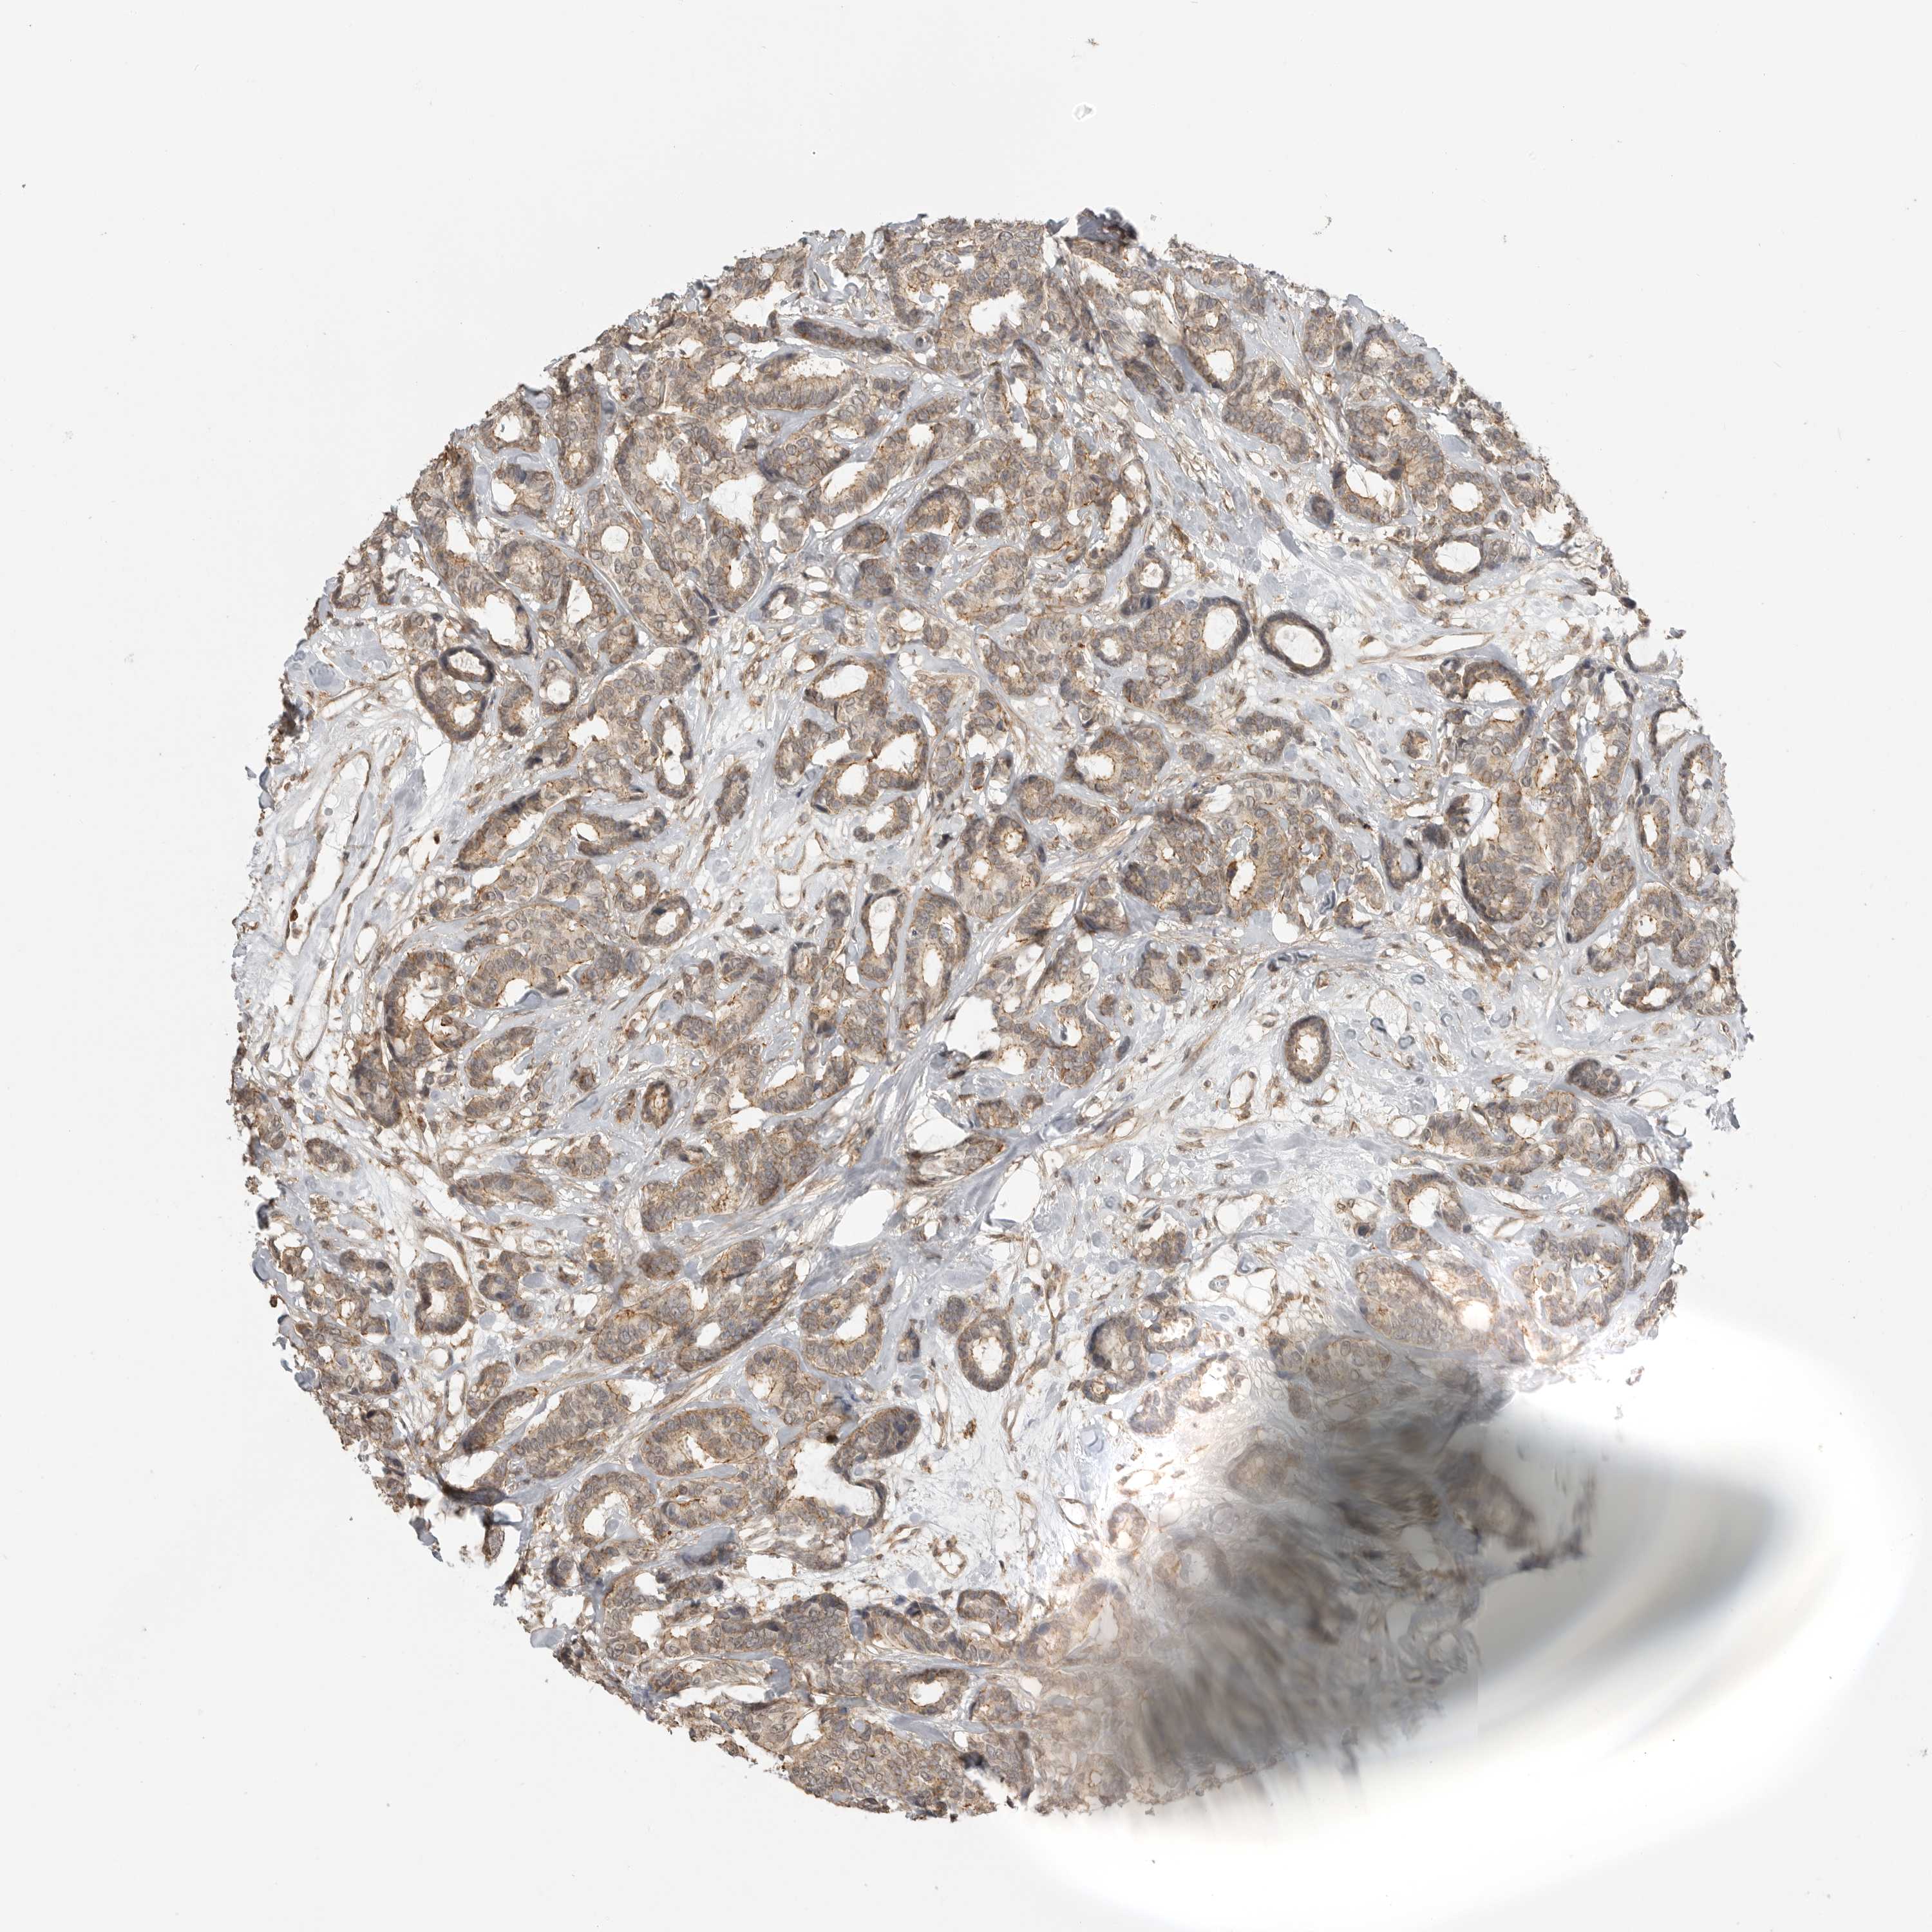

CANCER BREAST CANCER Show tissue menu

BRCA TCGA BRCA VALIDATION PROTEIN EXPRESSION